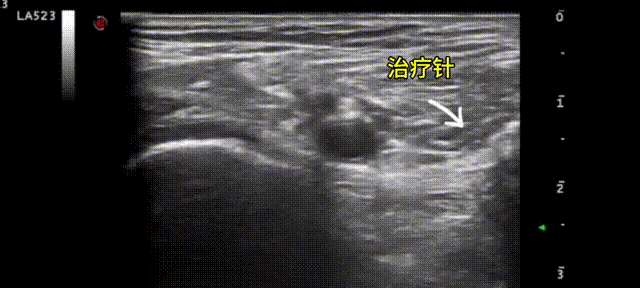

在超聲下進行全程可視化精準靶點治療

該技術利用高頻超聲探頭清晰顯示肌肉、骨骼等組織的結構和微病變,在超聲引導下精準定位、實時將藥物注射至病灶位置進行微創治療。